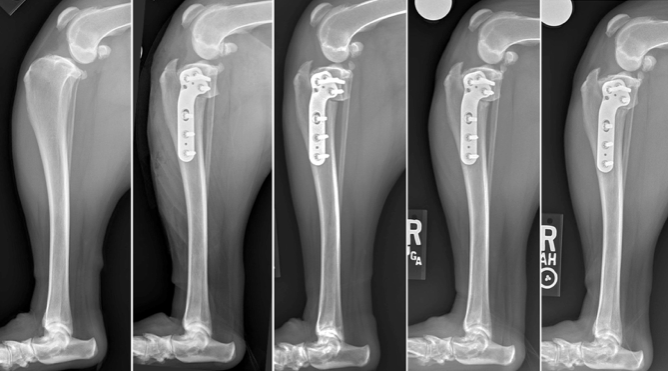

Once the surgery is performed the bone (tibia) needs to heal. This takes time, typically about 10 weeks. Below are a series of X-rays showing dog TPLO surgery recovery week-by-week. Note that we usually do not take X-rays at multiple time points following TPLO surgery, but this patient was part of one of Dr. Franklin’s published research projects closely evaluating bone healing, so multiple radiographs (X-rays) were taken for those patients.

Figure. Dog TPLO surgery recovery week-by week. The images above show a patient immediately prior to surgery, immediately following surgery, and then at 4, 7, and 10 weeks following surgery. What we can see is that where the bone was cut was still visible at 4 and 7 weeks following TPLO surgery but that this had filled in with new bone (ie was healed), at 10 weeks following surgery.